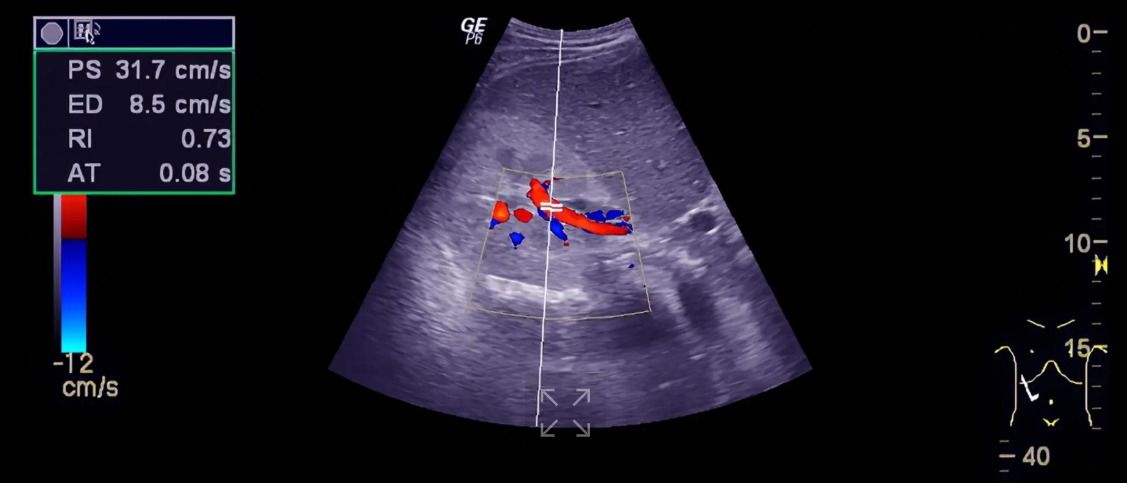

Dopplerul color arată fluxul sanguin sub formă de culori, evidențiind eventualele refluxuri sau turbulențe. Dopplerul pulsat și continuu măsoară viteza exactă a sângelui și ajută la evaluarea severității unor afecțiuni, precum stenozele sau insuficiențele valvulare. Aceste tehnici se completează reciproc pentru un diagnostic cât mai precis.